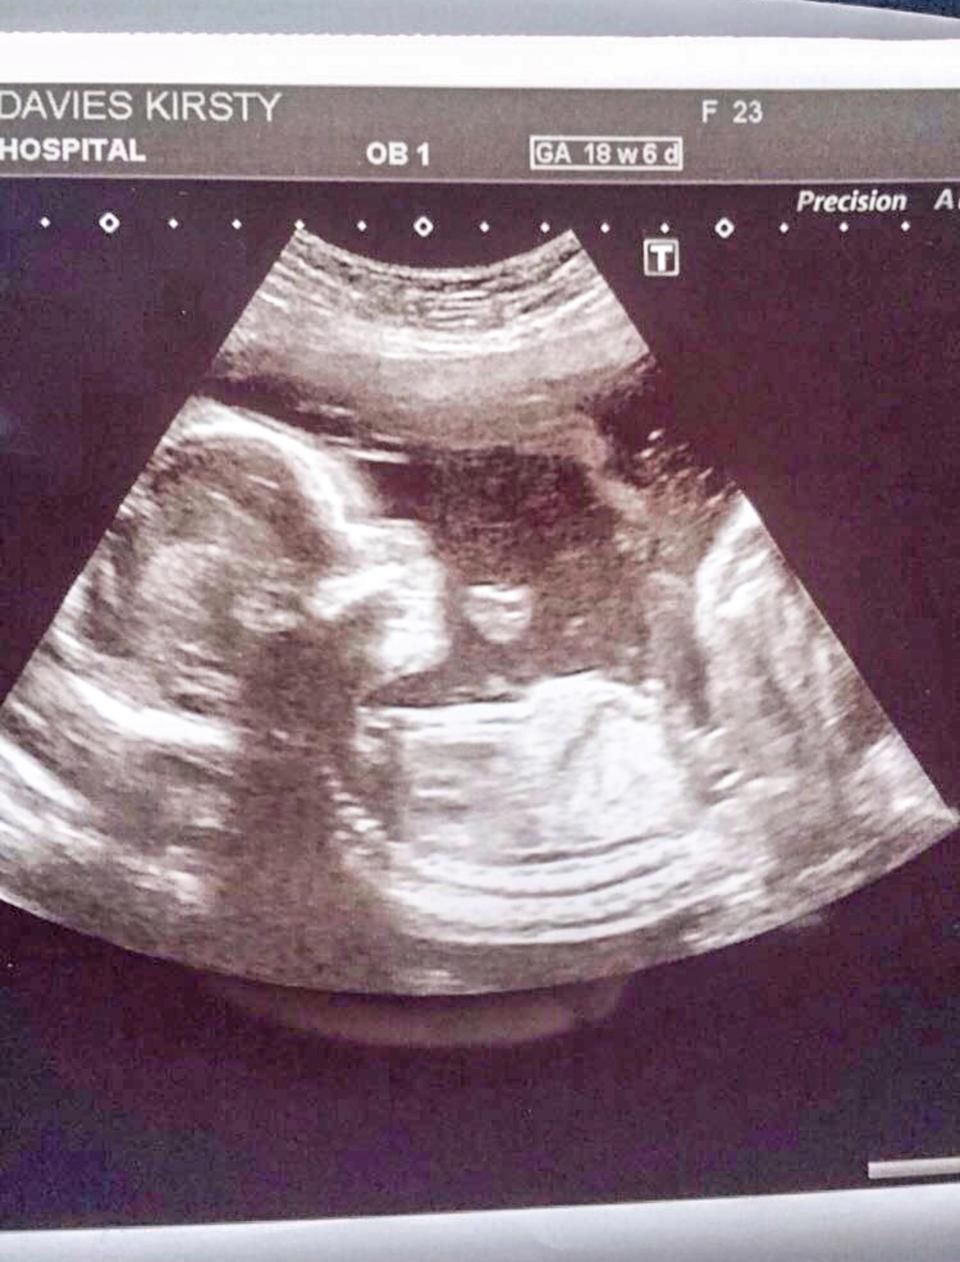

A 25 éves Kirstie Davies ultrahangján fura dolgot fedezett fel terhessége idején. A nő ugyanis puszit dobó emojinak látta három hónapos magzatát, aki szerinte így akarta tudatni vele, hogy minden rendben. A kismama azért vette ezt jó jelnek, mert babája amúgy kisebb volt a kelleténél.

„Megnyugtató volt számomra, mintha azt mondta volna nekem, hogy jól van. Úgy éreztem, hogy a kislányom boldog és egészséges bennem.”

A baba azóta megszületett, egészséges és jól van. Viszont anyja szerint nagyon érdekes, hogy minden búcsúzáskor puszit dob az emberek felé, épp úgy, ahogy az ultrahangfelvételen tette anno.